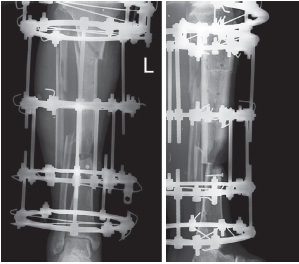

На 15-е сут. после приживления трансплантата выполнена операция: частичное удаление стержневого аппарата, в каждом отломке оставлено по одному стержню с целью сохранения положения голени, фиксация большеберцовой кости шарнирно-дистракционным аппаратом Илизарова (рис. 4, 5).

Рис. 4. Вид конечности на 1-е сут. после операции: правая голень фиксирована шарнирно-дистракционным аппаратом Илизарова

Figure 4. View of the lower extremity on the 1st day after surgery: the right lower leg is fixed with the Ilizarov hinged-distraction apparatus

Рис. 5. Рентгенограммы голени в прямой и боковой проекциях после фиксации шарнирно-дистракционным аппаратом Илизарова, угол рекурвации составил 24º

Figure 5. X-rays of the lower leg in frontal and lateral projections after fixation with the Ilizarov hinged-distraction apparatus, the recurvation angle was 24º

В течение следующих 8 дней выполнено устранение ангуляции голени с последующей кортикотомией большеберцовой кости в верхней трети (рис. 6). Через 30 дней начата дозированная тракция в аппарате в зоне остеотомии с целью устранения укорочения методом Илизарова (темп дистракции 1 мм в сутки).

Рис. 6. Рентгенограммы голени в прямой и боковой проекциях после остеотомии большеберцовой кости в верхней трети

Figure 6. X-rays of the lower leg in frontal and lateral projections after osteotomy of the upper third of the tibia

Через 3 мес. длина голени была восстановлена (рис. 7). Так как сохранялся дефект по передней поверхности большеберцовой кости, выполнено формирование краевого «отщепа» от перемещенного фрагмента с целью замещения дефекта (так называемая маргинальная пластика) (рис. 8).

Рис. 7. Рентгенограммы голени в прямой и боковой проекциях после восстановления длины конечности: созревающий регенерат большеберцовой кости

Figure 7. X-rays of the lower leg in frontal and lateral projections after restoration of limb length: maturing tibial regenerate

Рис. 8. Рентгенограммы голени в прямой и боковой проекциях после формирования краевого «отщепа» большеберцовой кости

Figure 8. X-rays of the lower leg in frontal and lateral projections after the formation of the marginal “split” of the tibia

Через 4,5 мес. достигнут контакт «отщепа» с дистальным отломком (рис. 9 а), а через 7,5 мес. отмечена хорошая перестройка регенерата (рис. 9 b).

Рис. 9. Рентгенограммы голени пациента в прямой и боковой проекциях в аппарате Илизарова из четырех колец: а — определяется контакт «отщепа» с дистальным отломком большеберцовой кости; b — определяется перестроившийся костный регенерат большеберцовой кости в верхней трети

Figure 9. X-rays of the patient’s lower leg in frontal and lateral projections in the Ilizarov apparatus with 4 rings: a — the contact between the “split” and distal fragment of the tibia is determined; b — the reconstructed bone regenerate of the tibia in the upper third is determined